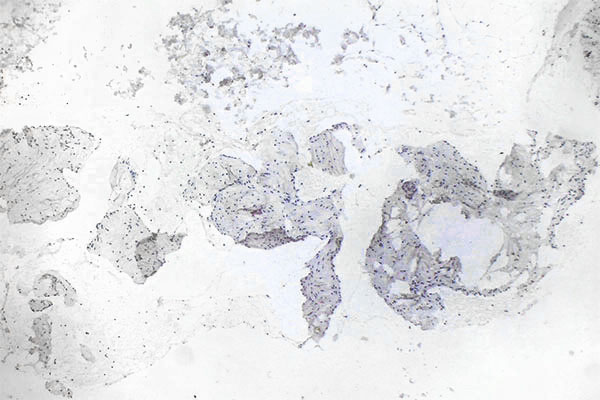

Histopathologischer Schnitt; die immunhistologische Färbung mittels MIB-1 auf das Ki67-Antigen ist eine klassische Färbung zur Darstellung der Proliferationsaktivität einer Läsion. Ki67 zeigt als Proliferationsmarker alle im weitesten Sinne in Teilung befindlichen Zellen an (außerhalb der G0-Phase im Zellzyklus).Hier sind nur sehr wenige teilungsaktive Kerne (hier ohne Mitosespindeln) als positive Kernfärbung nachweisbar. Damit sehr geringe Proliferationsrate als Hinweis auf eine benigne Läsion.